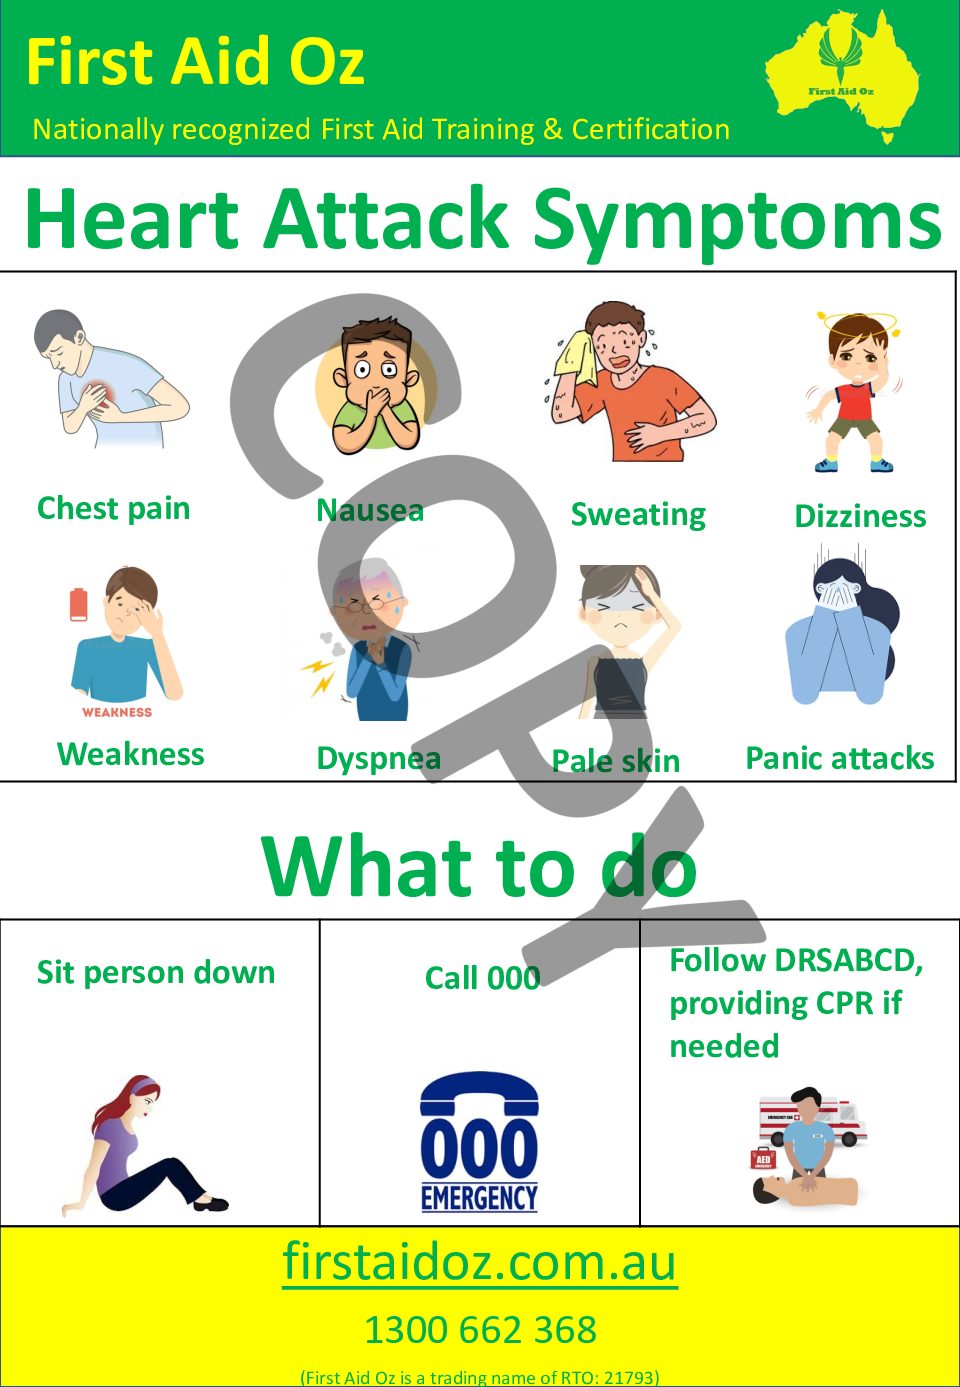

Heart Attack Poster First Aid Oz